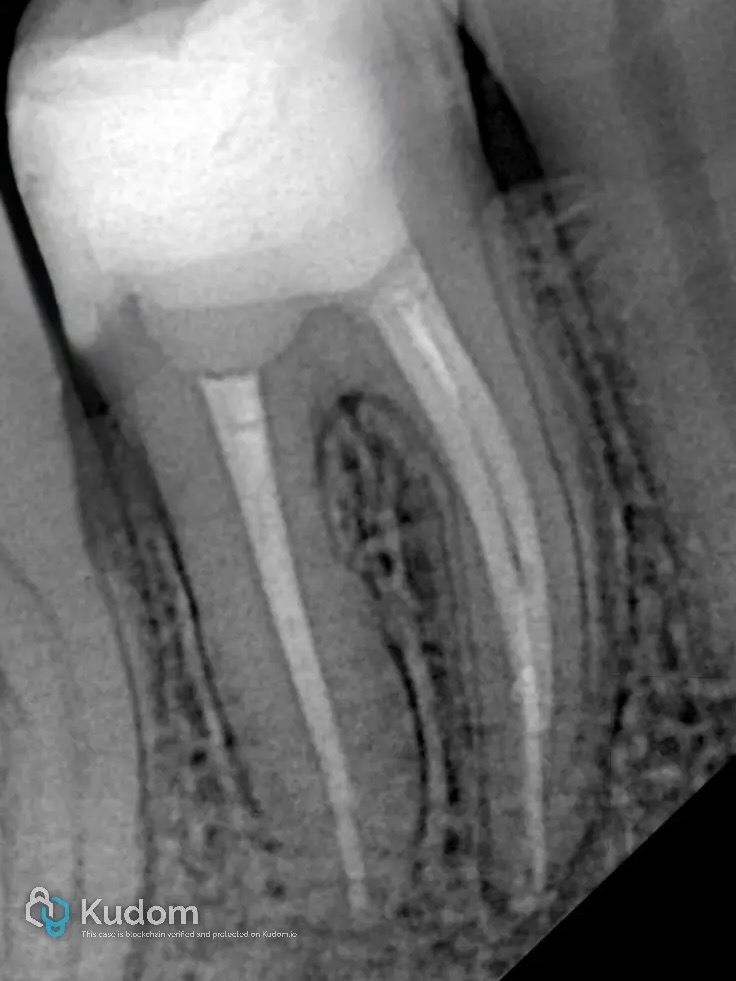

4. Obturation

- Warm vertical compaction technique

- Dense 3D obturation

- Radiographic confirmation

Immediate coronal sealing followed.

Radiographic Outcome

Postoperative radiographs confirmed:

- Dense obturation

- Well-adapted coronal seal

- Proper proximal contour

- No marginal overhang